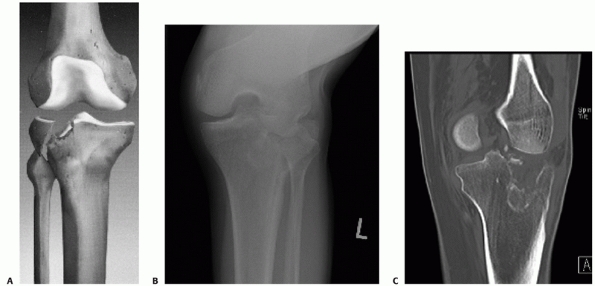

made on plain radiographs, and for some fractures this may be the only

imaging necessary. Anteroposterior (AP), lateral, and an AP view in the

plane of the plateau (10- to 15-degree caudal view) are the standard

examinations (Fig. 53-4). The caudal view

provides a better view of the articular surface and helps assess

displacement and depression better than the standard AP view.82,115

Hohl found that the standard AP view could not reliably determine the

amount of articular depression but that a 14-degree caudal view

accurately estimated central and posterior displacement but could

overestimate anterior displacement and depression.115

![]() |

FIGURE 53-4 A.

Anteroposterior radiograph of this patient after treatment of a tibial plateau fracture shows slight ellipses of the nonprofiled medial and lateral plateaus. The anterior margin projects more superiorly than the posterior margin. In the 10-degree, caudal view (B), the proximal articular surface is nearly a single radiodense line, providing better assessment of the articular surface. |